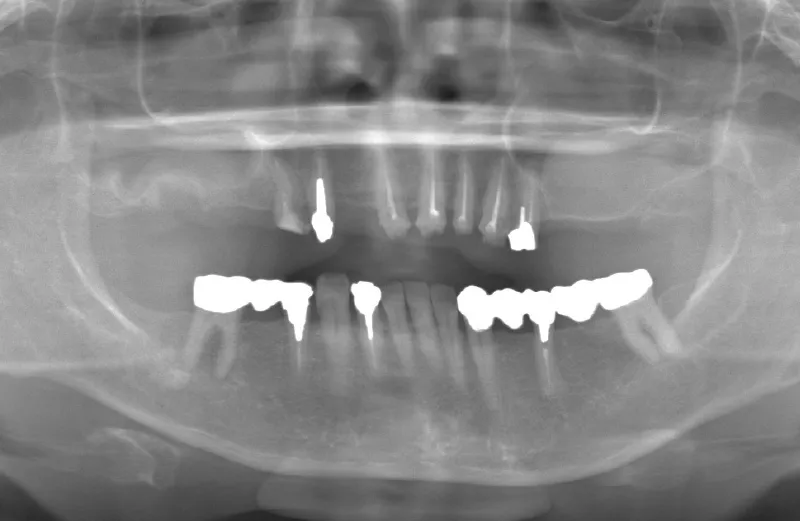

メガジェンオペの症例紹介01

治療前

治療後

| 主訴 | 入れ歯は以前に入れたことがあるが違和感が強く入れられなかったので右上左上をインプラントで治療して欲しい。 左上は他院では上顎洞までの垂直骨量が1mm程度しかないのでサイナスリフトが必須であり、インプラント治療で歯が入るまでに1年以上かかると言われたのでセカンドオピニオンを希望で来院。 |

| 治療期間 | 右上は2.5ヶ月、左上は3.5ヶ月で仮歯が入り、 4.5ヶ月で最終補綴物が入って終了。 |

| 治療費 | 約2,300,000円 |

| 治療内容 | エクストラワイドショートインプラントを埋入し、上顎洞を移植材を用いずに挙上しインプラントを埋入した。仮歯を装着し、様々な機能面に問題がないことを確認し4.5ヶ月で最終補綴物を装着して終了した。 |

| 治療の リスク |

インプラント埋入オペ時に術者が上顎洞内にインプラントを迷入させる可能性がある。これは術者が技術的に熟練していれば防ぐことが可能。 |